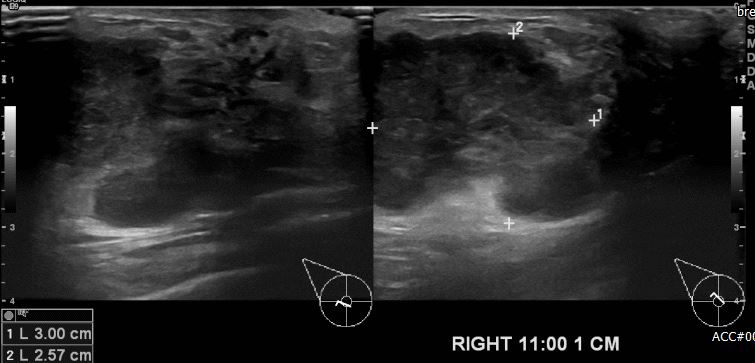

상기 환자 우측 유방에 만져지는 멍우리로 내원하신 20대 여성 분으로  우측 11시 방향

1cm 떨어진 거리의 혹 조직검사 시행하여 우측 침윤성 유관암 진단 되었습니다.